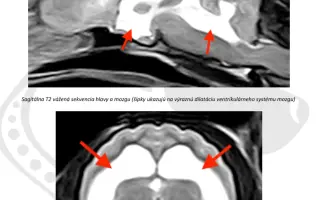

Aby sme vedeli, ako ďalej pokračovať v liečbe, potrebuje MRI vyšetrenie hlavy a odber mozgovomiechového moku.

Peniaze z tejto kampane budú použité na MRI vyšetrenie hlavy odber mozgovomiechového moku, ktoré nám ukáže, či Zoja nemá trvalé poškodenie mozgu alebo skrytý zápal.

Bez tohto vyšetrenia nevieme, či liečba, ktorá trvá už viac ako 50 dní, skutočne pomáha – alebo len bojujeme so symptómami.